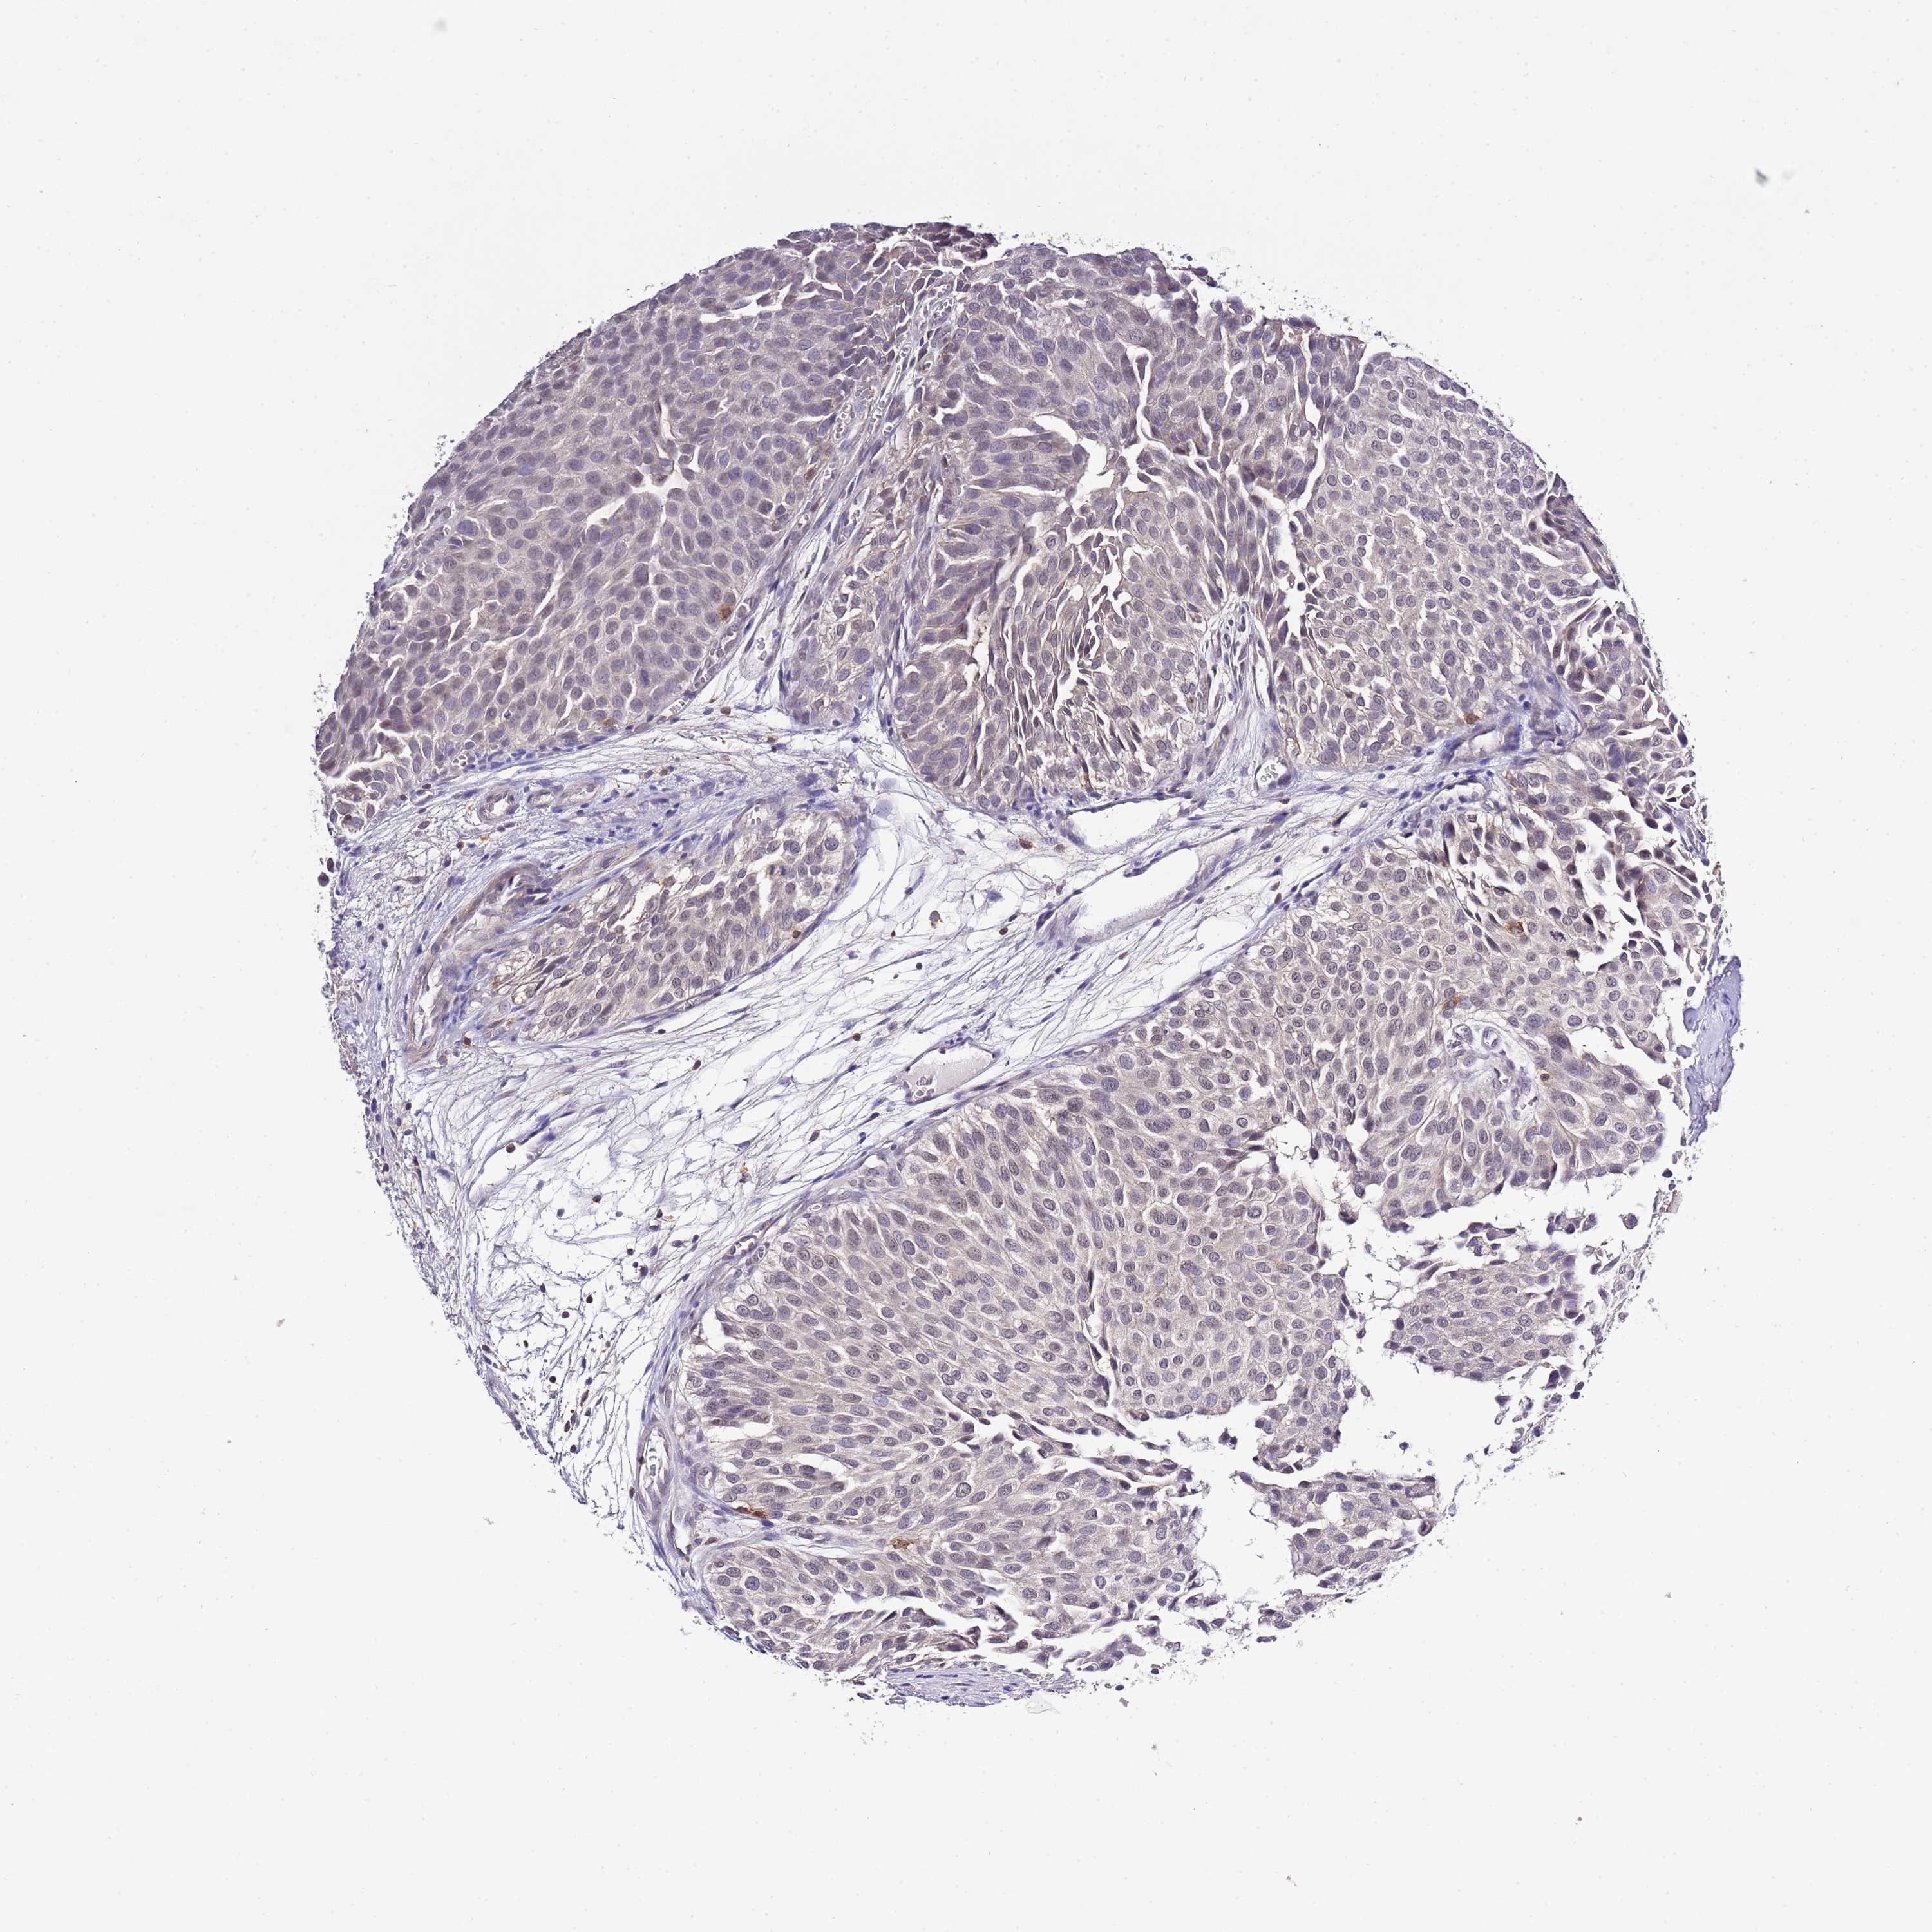

UROTHELIAL CANCER - Protein expressioni

A mouse-over function shows sample information and annotation data. Click on an image to view it in a full screen mode. Samples can be filtered based on level of antibody staining by selecting one or several of the following categories: high, medium, low and not detected. The assay and annotation is described here.

Note that samples used for immunohistochemistry by the Human Protein Atlas do not correspond to samples in the TCGA dataset.

Antibody stainingi

Antibody staining in the annotated cell types in the current human tissue is reported as not detected, low, medium, or high, based on conventional immunohistochemistry profiling in selected tissues. This score is based on the combination of the staining intensity and fraction of stained cells.

Each image is clickable and will lead to virtual microscopy that enables deeper exploration of all samples and also displays staining intensity scores, fraction scores and subcellular localization as well as patient and tissue information for each sample.

Antibody HPA049331

Antibody HPA056959

Urothelial carcinoma, Low grade

Urothelial carcinoma, High grade

Urothelial carcinoma, NOS